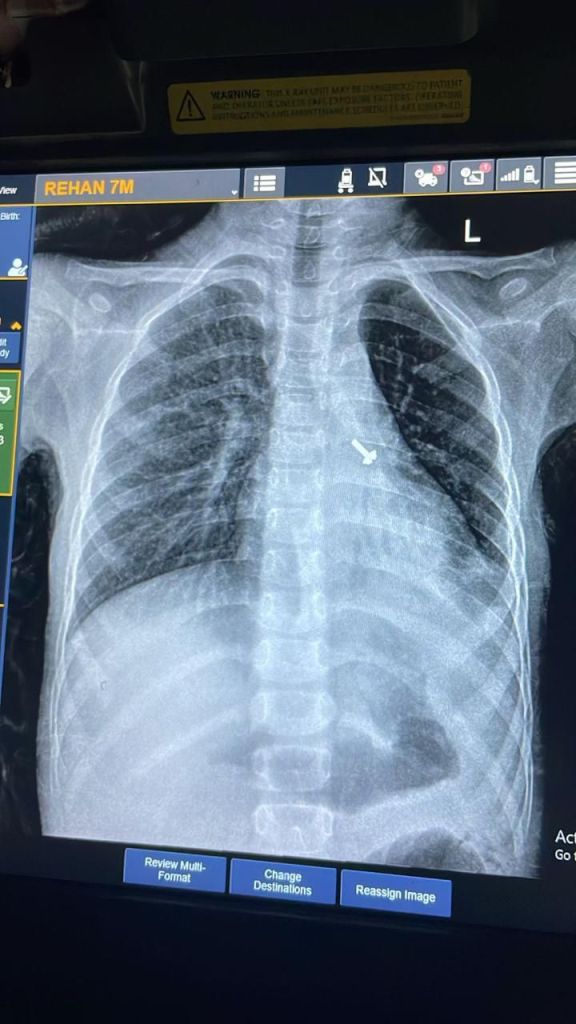

बालरोग विशेषज्ञ डॉ. व्यास कुमार राठौड़ के मुताबिक बच्चे की कुछ प्रारंभिक जांचें कराई गईं, जिसमें उसकी छाती के एक्स-रे एवं सीटी स्कैन में बच्चे के फेफड़े में एक पेंच दिखाई दिया है । इस विषय में चिकित्सक द्वारा बच्चे के अभिभावकों से पूछे जाने पर उन्हें बताया गया कि बच्चे ने घर में खेल-खेल में पेंच निगल लिया, जिसका पता परिजनों को नहीं लग पाया ।

पल्मोनरी मेडिसिन विभाग की आचार्य डॉ. रुचि दुआ के अनुसार हमारे विभाग को संस्थान के बालरोग विभाग के चिकित्सक डॉ. व्यास कुमार राठौड़ की ओर से जानकारी प्राप्त हुई कि भरत नगर, रुड़की हरिद्वार निवासी एक 07 वर्ष के बच्चे रेहान को उसके परिजन ओपीडी में परीक्षण के लिए लाए हैं, जिसकी जांच में ज्ञात हुआ है कि बच्चे के फेफड़े में पेंच फंसा हुआ है ।